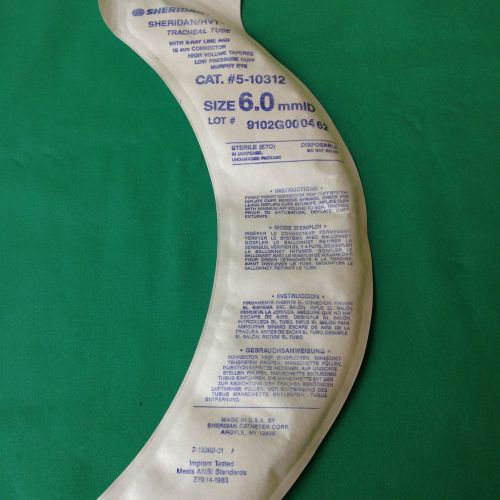

SHERIDAN/HVT TRACHEAL TUBE 5-10310 6.0mm Low Pressure Cuff Murphy